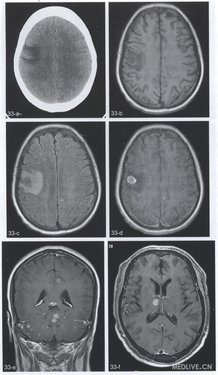

【简要病史】4个病例。例1(图33a~e),女,54岁。乳腺癌术后1年,头痛、言语不清、肢体麻木1周。例2(图33f,g),男,59岁。头痛2个月。例3(图33h),女,50岁。头痛、右听力下降1个月。例4(图33i),右侧颈部恶性黑色素瘤术后2个月头痛。

【CT与MRI所见】例l(图33a),CT平扫显示右侧额叶局限性低密度灶。T1WI(图33b)病变呈圆形,边缘信号较高。FLAIR序列(图33c)幕L脑实质多发高信号灶。增强T1Wl(图33d,e)幕上、下脑实质多发结节状及点状强化灶。例2,轴位增强T1WI(图33f)右丘脑腹内侧结节状明显强化灶。胸部CT(图33g)显示左肺尖结节。例3,轴位T2WI(图33h),右侧桥臂稍高信号肿块。例4,矢状位T1WI(图33i)显示右侧额叶类圆形病变,内见高信号成分。

【手术后病理诊断】例1,乳腺癌脑实质多发转移。例2,细支气管肺泡癌右侧丘脑转移。例3,右侧桥臂转移瘤(来源不明)。例4,右额叶恶性黑色素瘤转移。